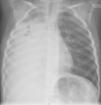

Ingresa en planta, se mantiene el tratamiento del hospital de origen y se realiza una radiografía de tórax en la que se observa una extensa opacificación del hemitórax derecho (fig. 1). Ante estos hallazgos, se continúa el estudio con una TC de tórax en la que se aprecian calcificaciones paratraqueales e hiliares derechas, consolidación subtotal del pulmón derecho con bronquiectasias, y obstrucción del bronquio principal derecho en su origen (fig. 2).